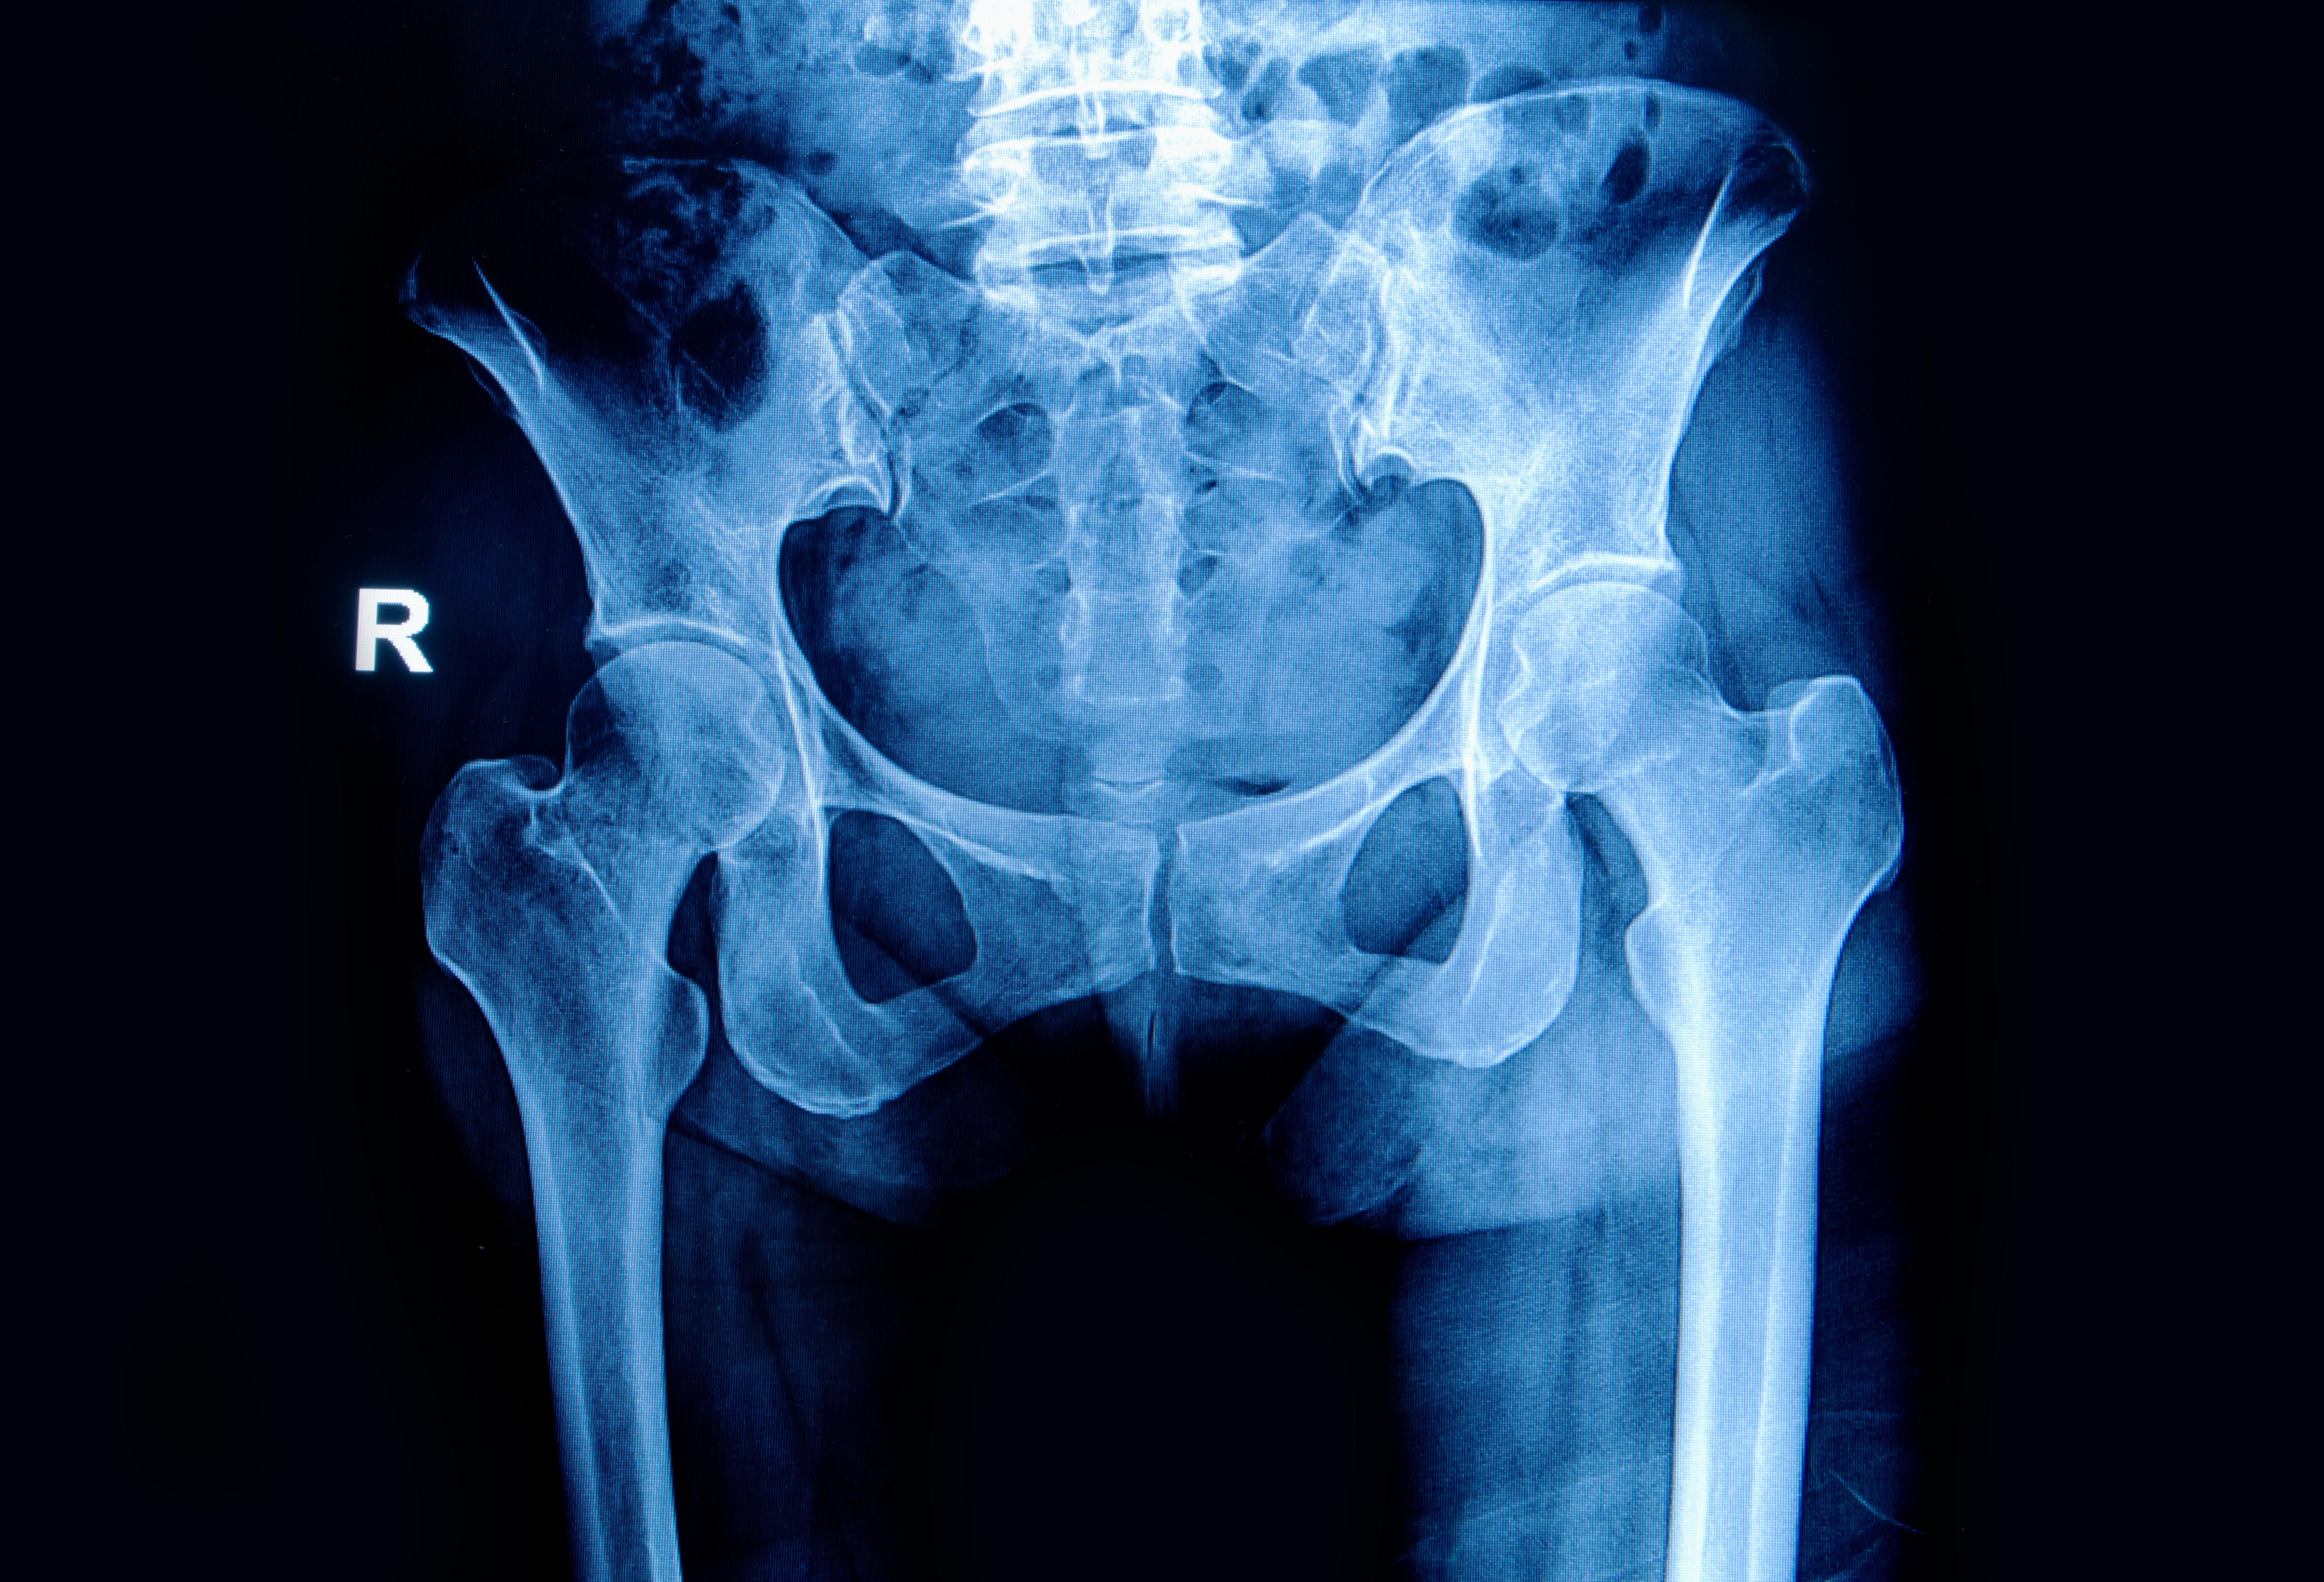

Photo: Colourbox

To sustain a hip fracture after the age of 65 is undoubtedly a significant strain on the body. It is already known that this patient group has a high mortality rate following a hip fracture. A recent study of 37,708 hip fractures in Norway from 2014 to 2018 shows that these patients have a considerably shorter life expectancy compared to a comparable segment of the population.